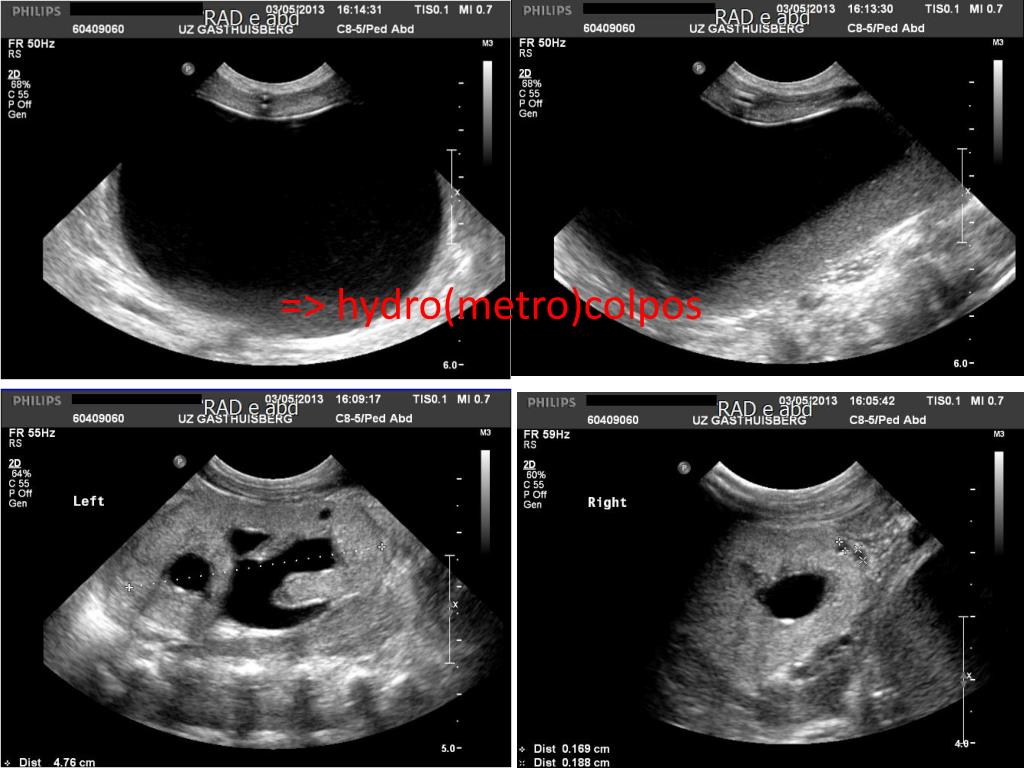

4. => hydro(metro)colpos

5. Congenitale defecten • Abdomen: • Hydro(metro)colpos (vaginaleatresie) • Enkelebilateralekleinerenalecorticalecystes • Ledematen: postaxialepolydactylie van de 4 ledematen • Ogen: fundoscopie: gele spots, nauwe bloedvaten (suggestief voor retinale dystrofie) • Cardiaal: klein ASD op D0 • Craniaal: normale echo’s D1, D7 => Bardet-Biedl syndroom